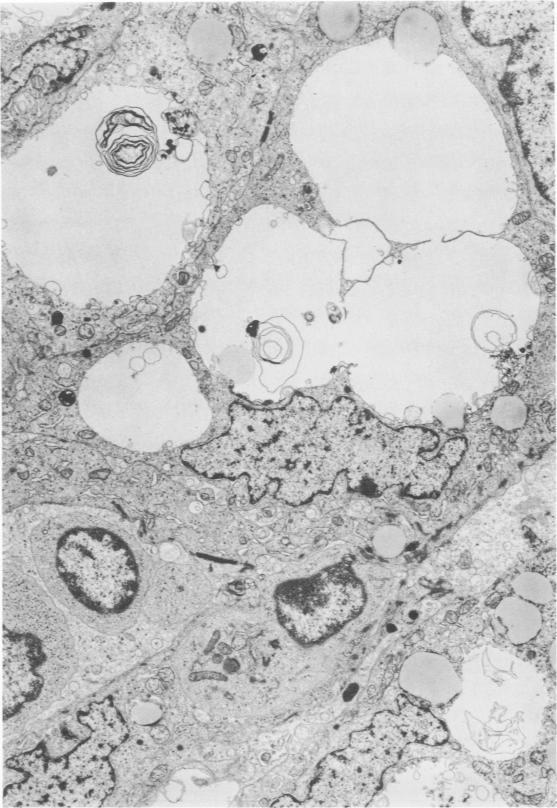

In this study, thymoma is defined as a neoplasm of the epithelial-reticular framework cells of the thymus. As in the normal thymus, these cells regularly displayed branching tonofilaments, macuale adherens, elongated processes, and basal lamina. These characteristics proved useful in the differential diagnosis of thymoma from a variety of anterior mediastinal tumors including thymic carcinoid, lymphoma, germinoma (seminoma type), and fibrous mesothelioma. Lymphocytes in the thymomas often showed mitotic activity and a moderate degree of transformation. The significance of this and the gland-like spaces, vacuolated epithelial cells, starry-sky appearance, emperipolesis, and perivascular spaces is discussed.